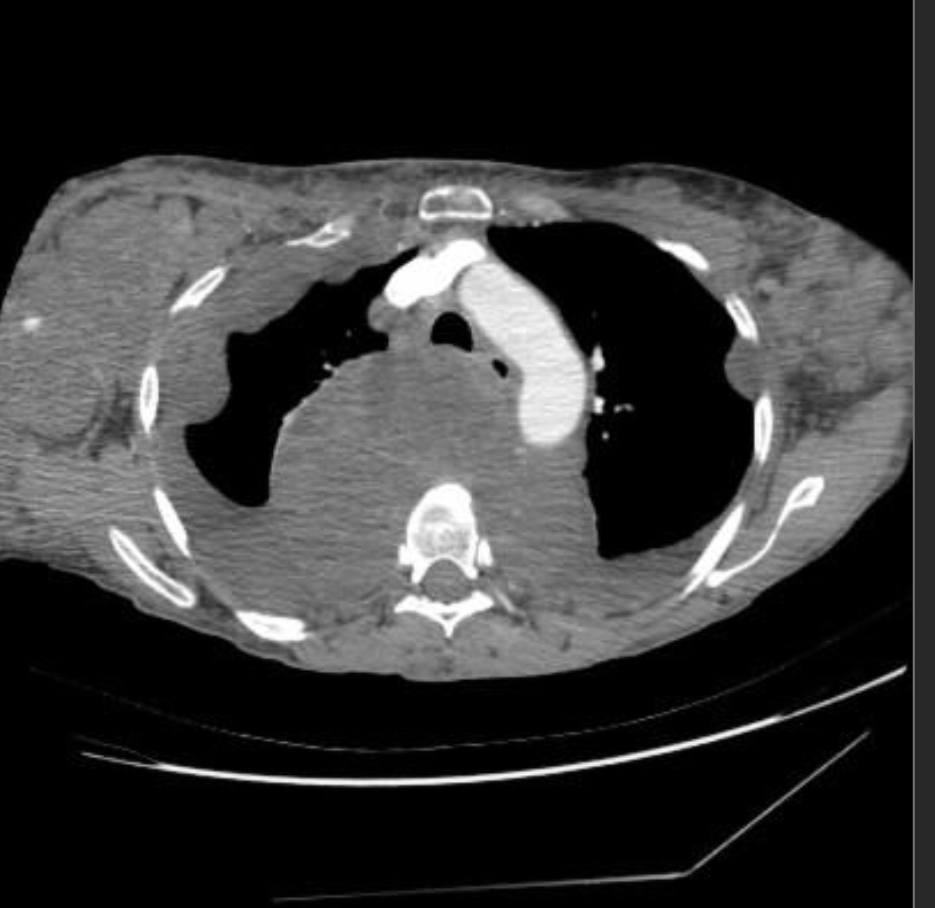

describe, and dx

chronic hypersensitivity pneumonitis

Mosaic pattern with areas of ground-glass atenuation and areas of low attenuation.

Fibrosis and parenchymal distortion in a mid zone distribution.

left vs right?

Left UIP w honeycombing

Right Chronic HP